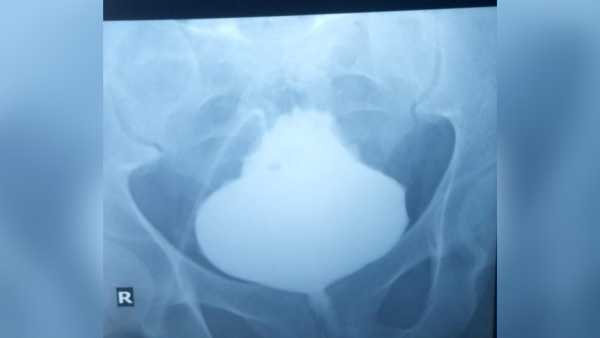

Individuals dealing with both color blindness and bladder cancer might encounter a less promising outlook compared to those who have bladder cancer but possess typical sight, a study reveals.(Image credit: lielos/Getty Images)ShareShare by:

Could the presence of color vision deficiency reduce your likelihood of surviving bladder cancer? This is the intriguing proposition that investigators have put forth, based on a limited investigation.

The study, appearing on Jan. 15 in the journal Nature Health, analyzed information from 135 individuals with concurrent bladder cancer and color blindness, and compared these individuals to 135 individuals affected solely by bladder cancer. The data was sourced from TriNetX, a global database of digital health records encompassing over 275 million individuals.

The researchers proposed a likely justification for this noted variation: Color blindness could complicate the detection of blood within your urine — an initial symptom of the malignancy — potentially delaying identification.

Blood present in urine represents one of the foremost early manifestations of bladder cancer, in conjunction with frequent urination, discomfort or burning sensations upon urination, the sensation of needing to urinate even when the bladder is not full, and regular nighttime urination.

Should anyone observe blood in their urine, they ought to promptly seek medical consultation, stated Kasivisvanathan. However, as the study authors posited, the inability to readily differentiate between red and yellow could significantly impede the recognition of this initial warning signal.